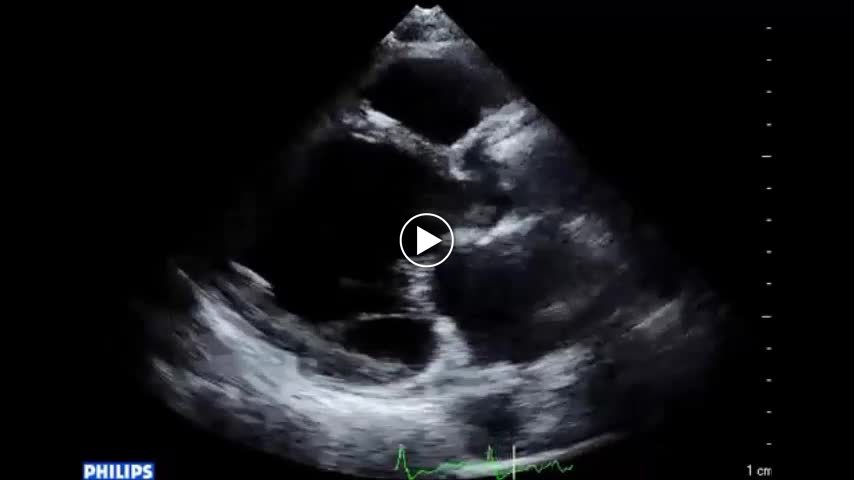

• 図5 拡張型心筋症患者の心尖拍動 b